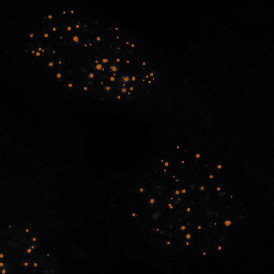

The RNA Scope App enables the detection of nuclei based on appropriate staining and dot detection per cell within nucleus and/or cytoplasm for one dot marker in CISH and SISH experiments . Each segmented cell compartment is measured for up to 20 intensity, statistic, and morphometric parameters. Dot parameters are provided per cell and per dot and include count, mean intensity, total dot area and the sum of intensity.

App Category 2